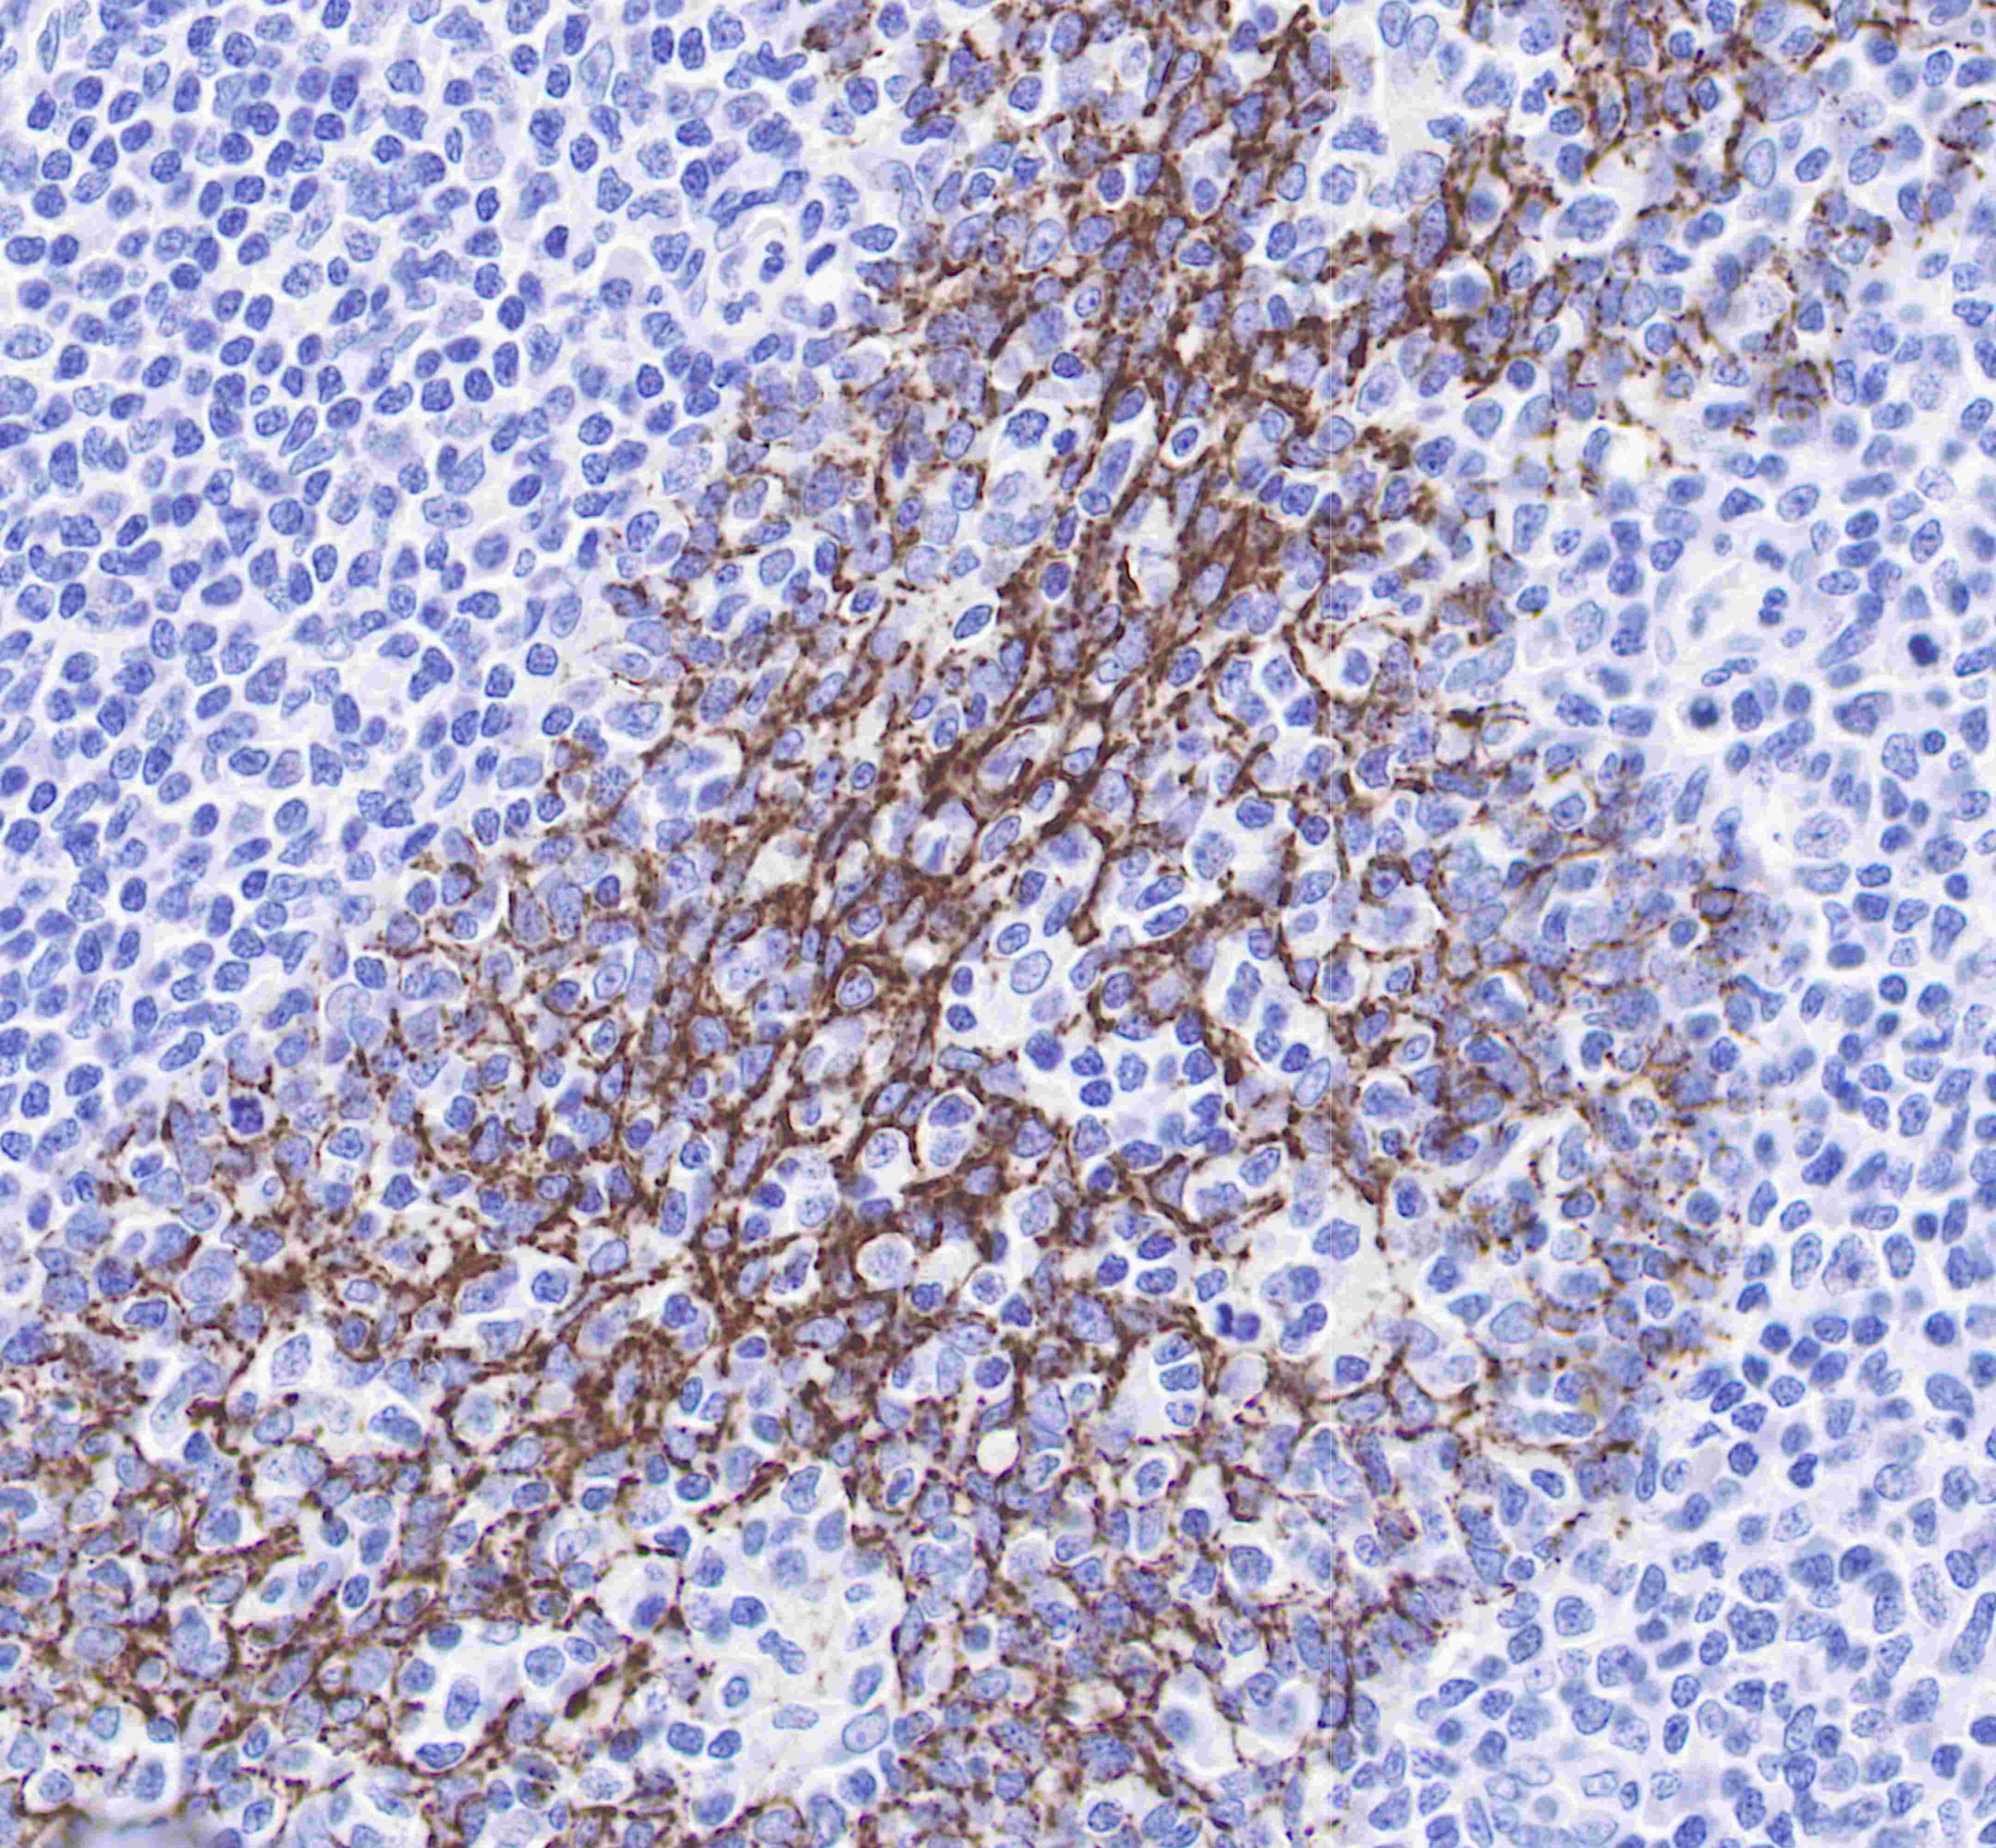

| IHC-P |

1:250 |

Claudin-1 is a protein that in humans is encoded by the CLDN1 gene.It belongs to the group of claudins.

Tight junctions represent one mode of cell-to-cell adhesion in epithelial or endothelial cell sheets, forming continuous seals around cells and serving as a physical barrier to prevent solutes and water from passing freely through the paracellular space. These junctions are composed of sets of continuous networking strands in the outwardly facing cytoplasmic leaflet, with complementary grooves in the inwardly facing extracytoplasmic leaflet. The protein encoded by this gene, a member of the claudin family, is an integral membrane protein and a component of tight junction strands. Loss of function mutations result in neonatal ichthyosis-sclerosing cholangitis syndrome.